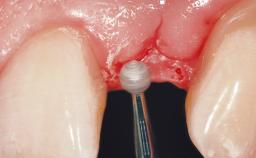

Immediate Flapless Placement of an Implant in a Maxillary Right Lateral Incisor Site

This 43-year-old male patient, a non-smoker, came to our practice because of a fracture of tooth 12 caused by a bicycle accident. Due to the combined para- and infrabony crown and root fracture, tooth extraction, and subsequent implant placement were suggested to the patient as the therapy of choice. The patient had high esthetic expectations with regard to the treatment outcome and asked for an immediate fixed provisional restoration. His individual esthetic risk profile summed up to a medium esthetic risk.

Placement Protocol Immediate implant placement

Loading Protocol Immediate

Provisional Implant-Supported Prosthesis Prosthodontic margin > 3 mm apical to mucosal margin Prosthodontic margin > 3 mm apical to mucosal margin